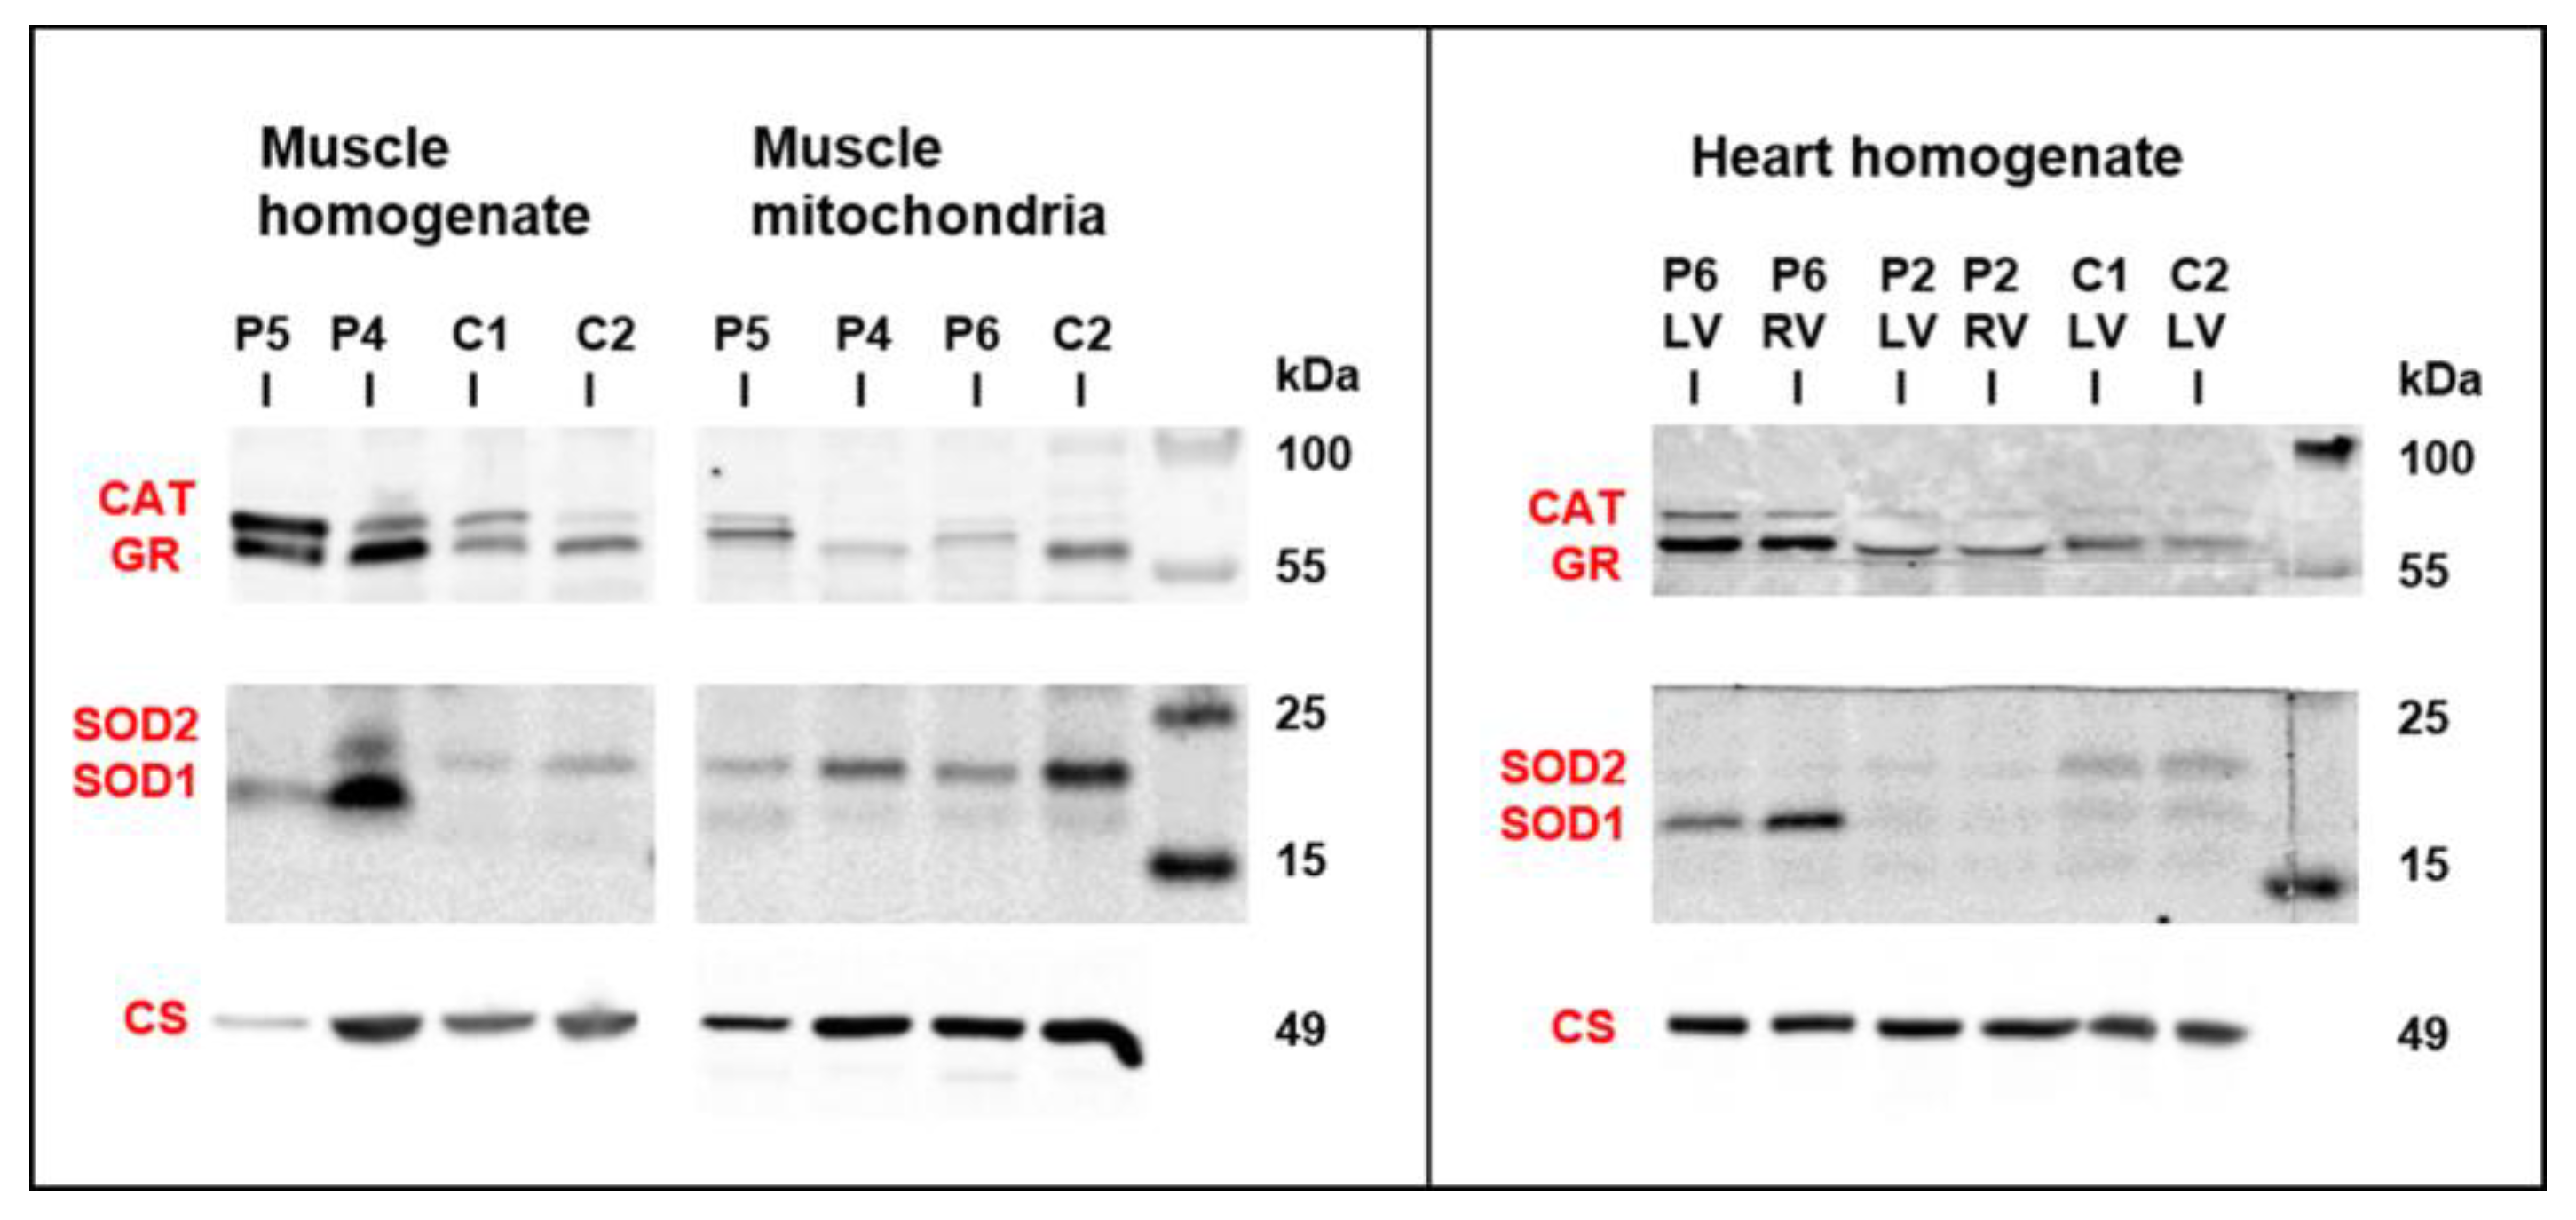

3.5. Mitochondrial Function and Content in Skeletal Muscle and Heart